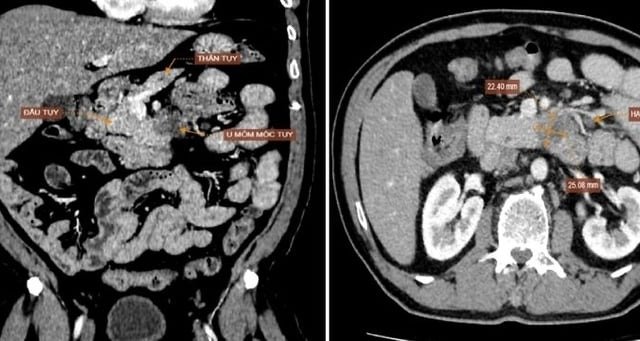

Đau bụng kéo dài, đi khám phát hiện ung thư giai đoạn cuối

Hai tháng đau bụng thượng vị, lan ra sau lưng, người đàn ông đi khám phát hiện ung thư tụy di căn gan, phổi, không...